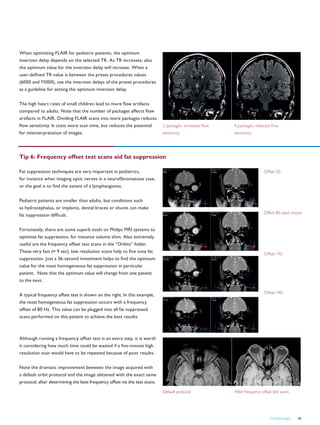

Professor of Radiodiagnosis, Cairo University, Egypt.

Advanced techniques enable broad use of Cairo Panorama HFO

Fetal Chiari malformation

Fetal MR images acquired at 37

weeks of pregnancy show Chiari

malformation. Performed on

Panorama HFO in Wadi El-Neel

Hospital, Cairo.

FieldStrength 33

Fiber tracking in spine

MR images show a focal

cervical cord area of

malacia. Fiber tracking

demonstrates fiber

interruption in that area.

Performed on Panorama

HFO in Wadi El-Neel

MR news

FieldStrength – Issue 39 – December 200934